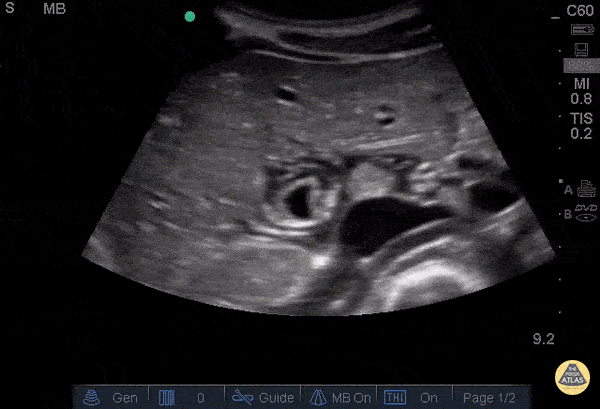

Biliary - Pericholecystic Fluid - Transverse

26 y/o F PMH HIV presents with non-bloody, non-bilious vomiting for one day associated with upper abdominal pain. POCUS revealed gallbladder wall thickening and pericholecystic fluid, but no gallstones or sonographic Murphy’s sign. The patient received symptomatic treatment and a surgical evaluation. The patient ultimately improved and was determined to not have cholecystitis. The patient was discharged home after her symptoms resolved and she was able to tolerate PO.   Dr. Guru Shan, Dr. Guy Carmelli, Dr. Scott Kendal - Kings County Emergency Medicine